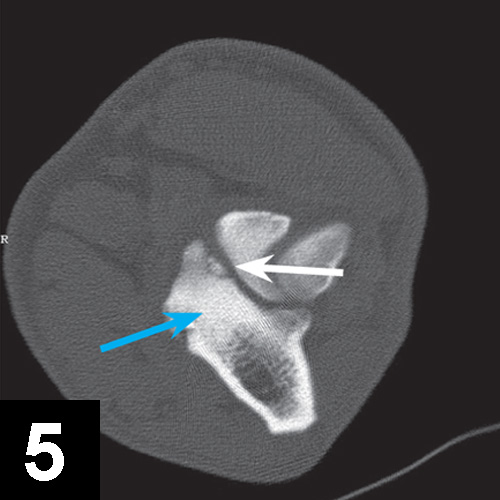

Elbow dysplasia is an umbrella term for several conditions (eg, ununited anconeal process [UAP], medial coronoid disease [MCD], osteochondrosis [OC]/OCD, incongruency) resulting in OA. Most patients are affected by only 1 or 2 of these conditions at the same time (eg, fragmented medial coronoid process, humeral OCD). The causes are multifactorial; genetic and environmental factors are involved. Dogs present with unilateral or bilateral lameness or stiffness of the forelimbs with effusion, pain, and decreased range of motion of the elbow. In dogs older than 5 months of age, radiographs of the joint may show a radiolucent line in the anconeal process (ie, UAP; Figure 3), an articular defect in the medial aspect of the humeral condyle (ie, OC, OCD; Figure 4), sclerosis and blunting of the medial coronoid process (ie, MCD), degenerative changes, or joint incongruency.

MCD (with or without fragment) is the most common among these conditions. Advanced imaging techniques (eg, CT) help in visualization of the coronoid process, which may appear fragmented or sclerotic (Figure 5), be associated with osteophytosis, or have radial incisure irregularities.

Mediolateral radiograph of the elbow in a 7-month-old German shepherd dog with joint effusion and pain of the elbow. A radiolucent line (arrow) can be observed between the anconeal process and proximal ulna, consistent with UAP.